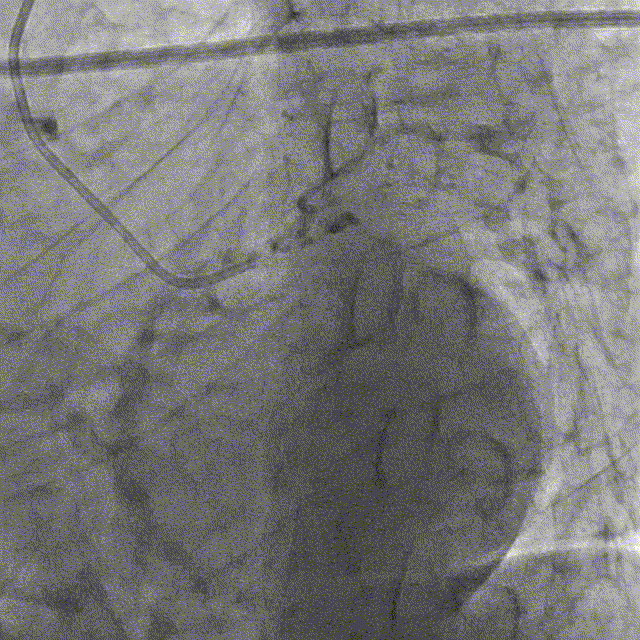

冠脉造影

冠脉造影结果:LM外膜钙化,内膜不光滑,中段狭窄90%,TIMI3级。LCX外膜钙化,内膜不光滑,TIMI3级。RCA外膜钙化,内膜不光滑,近段狭窄80%,中段狭窄90%,可见破损斑块,TIMI3级。

冠脉内介入治疗